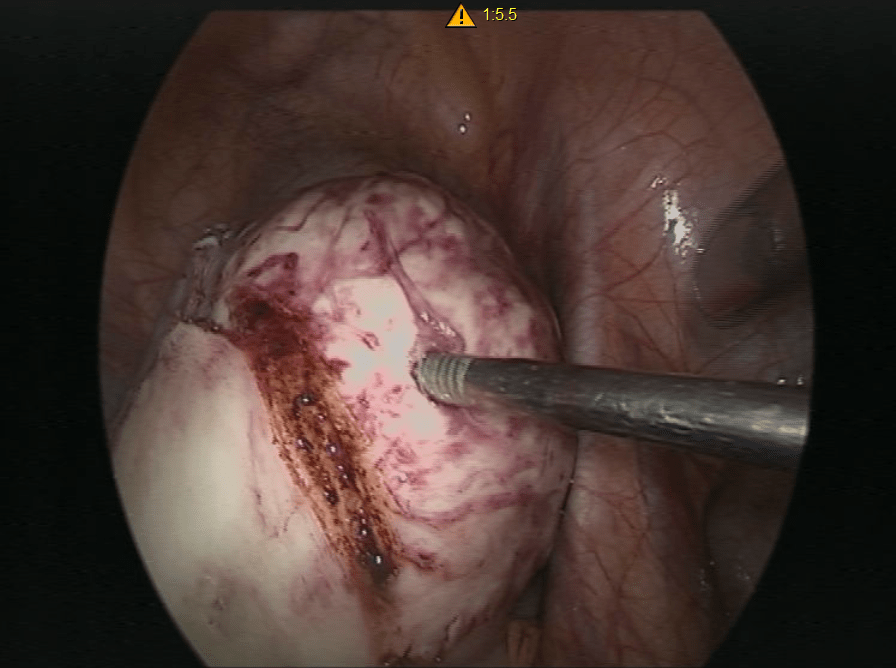

Not all fibroids require treatment, but problematic, large, or growing fibroids need medical intervention. Laparoscopy is a minimally invasive surgical approach that offers an effective solution for fibroid removal. This technique allows for the removal of even large and multiple fibroids with minimal discomfort and quicker recovery times.

High-definition cameras and instruments ensure accurate removal.

Depending on the patient’s age and desire to have children, laparoscopic surgery can involve the removal of just the fibroids or, in some cases, the uterus. Each treatment plan is tailored to the individual needs of the patient.